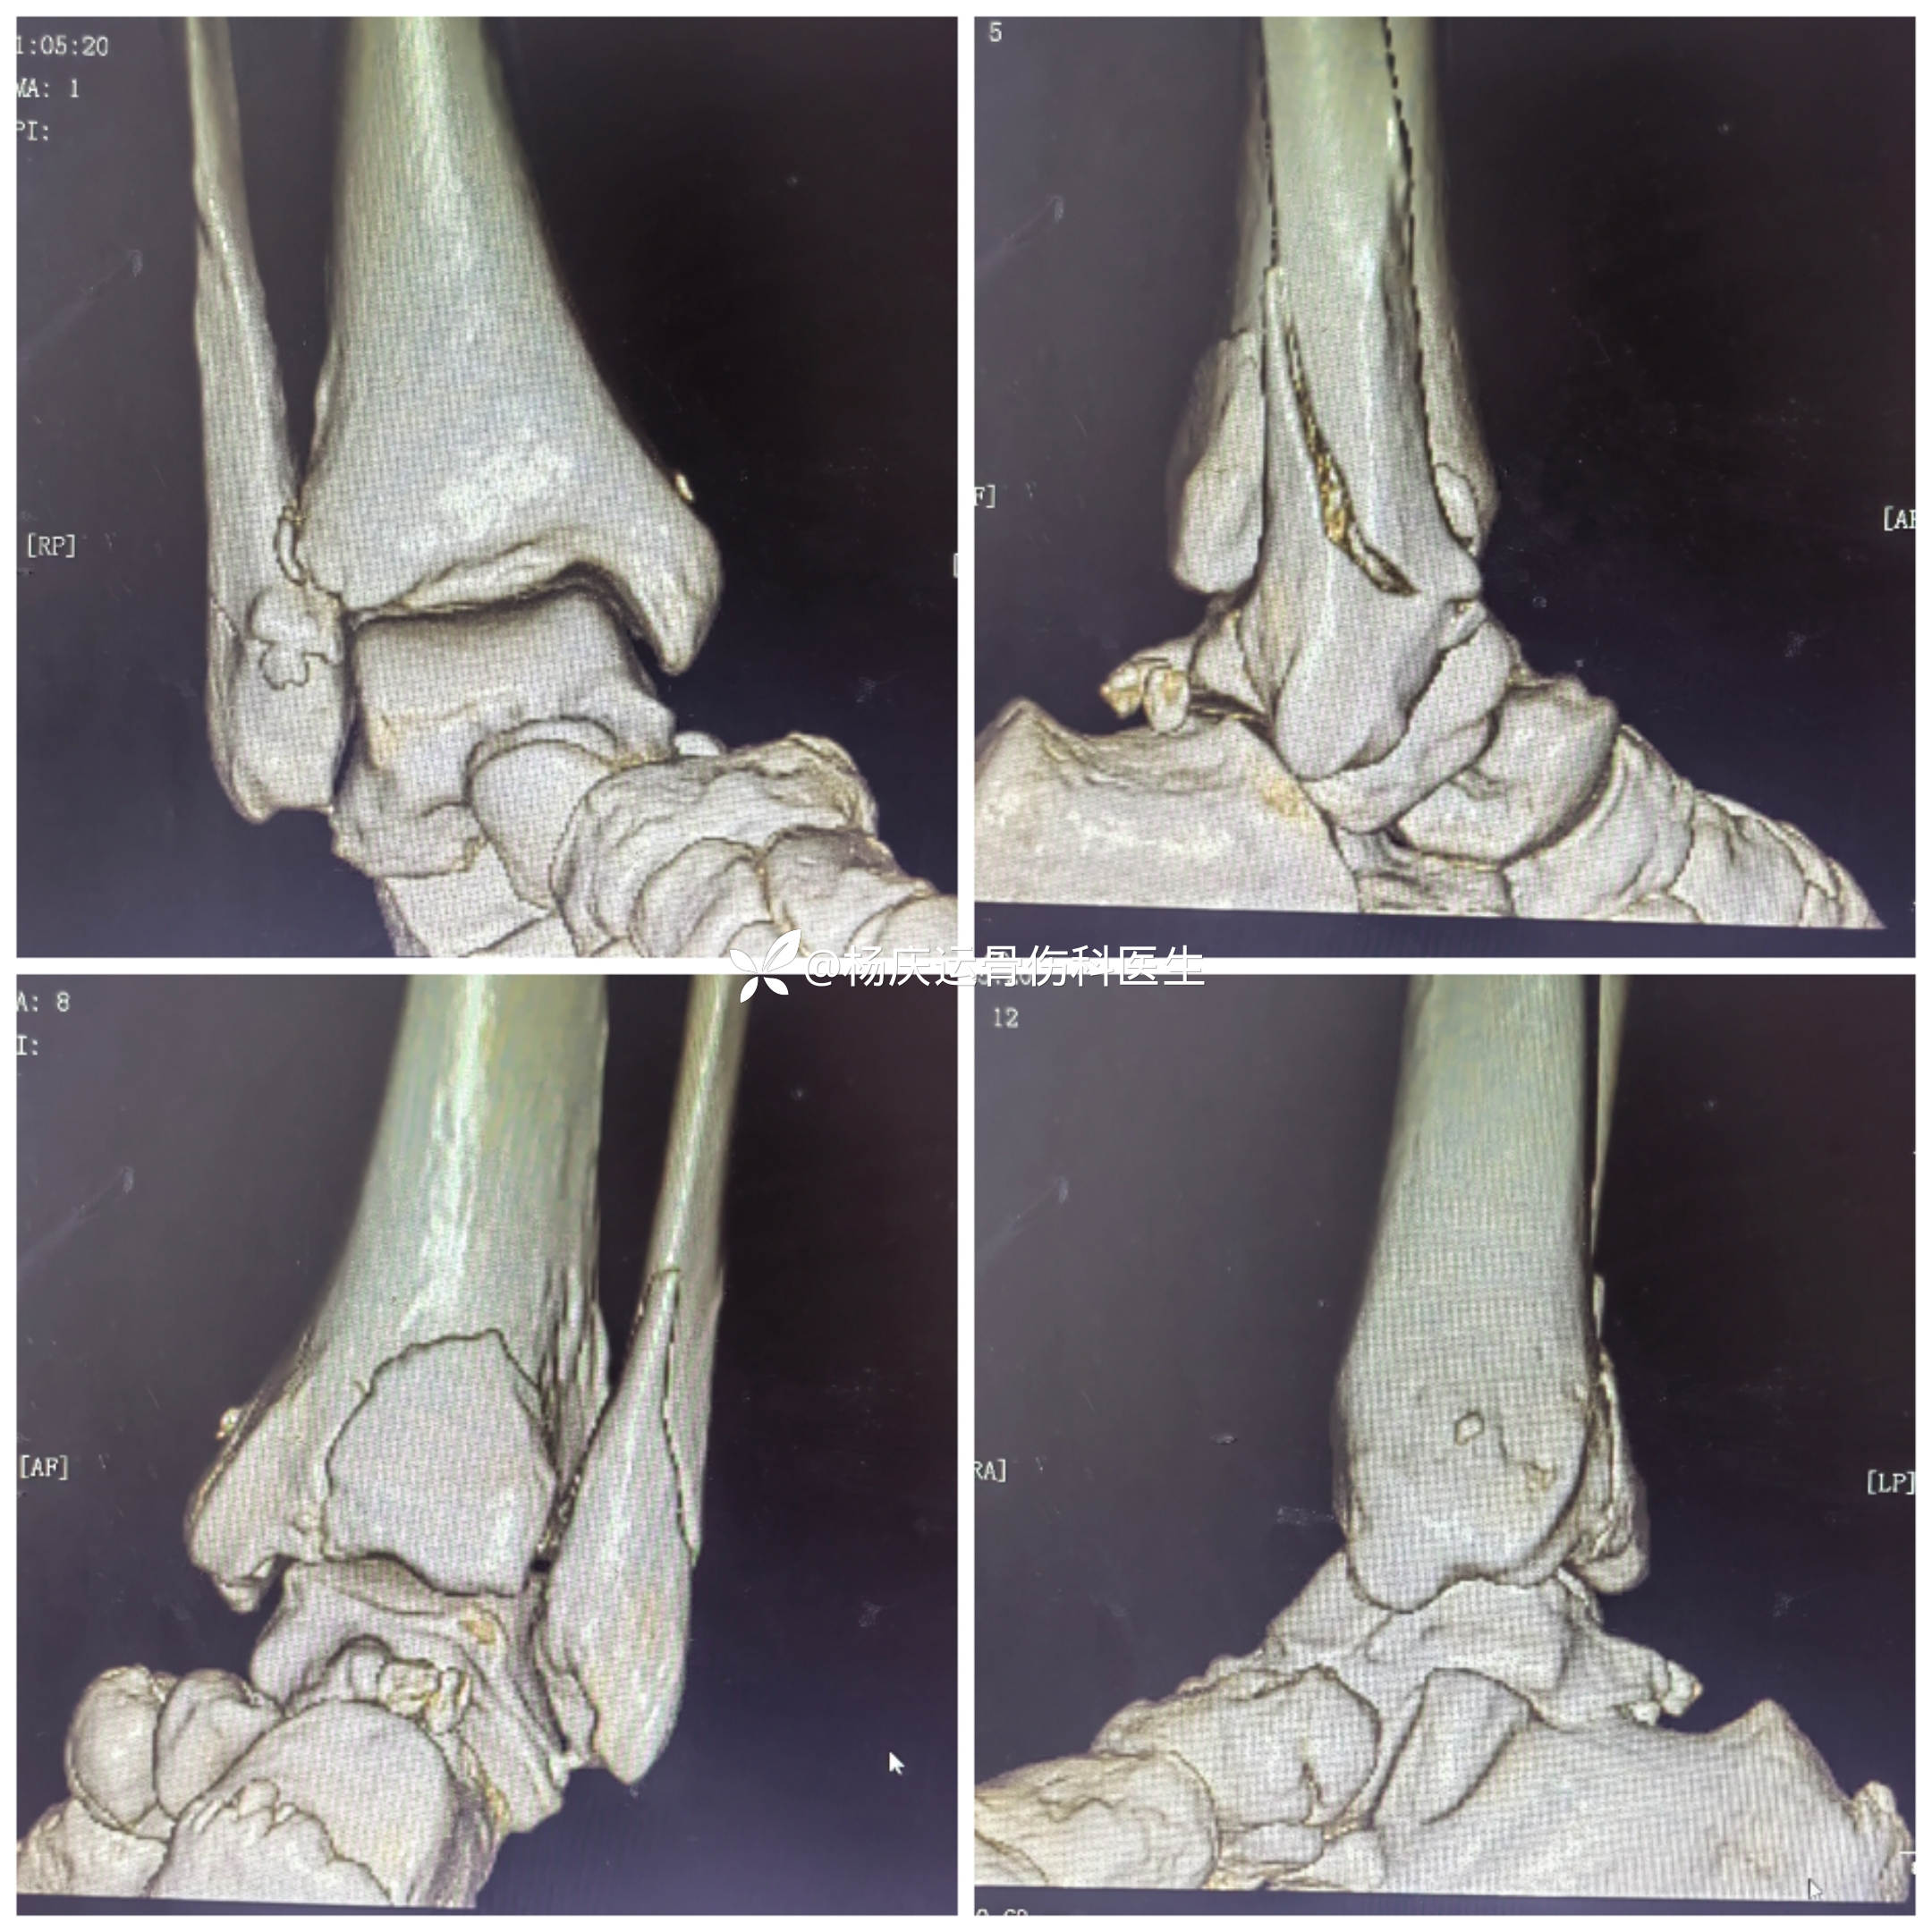

首诊三维CT

3天复查CT

关节面台阶约1.0mm